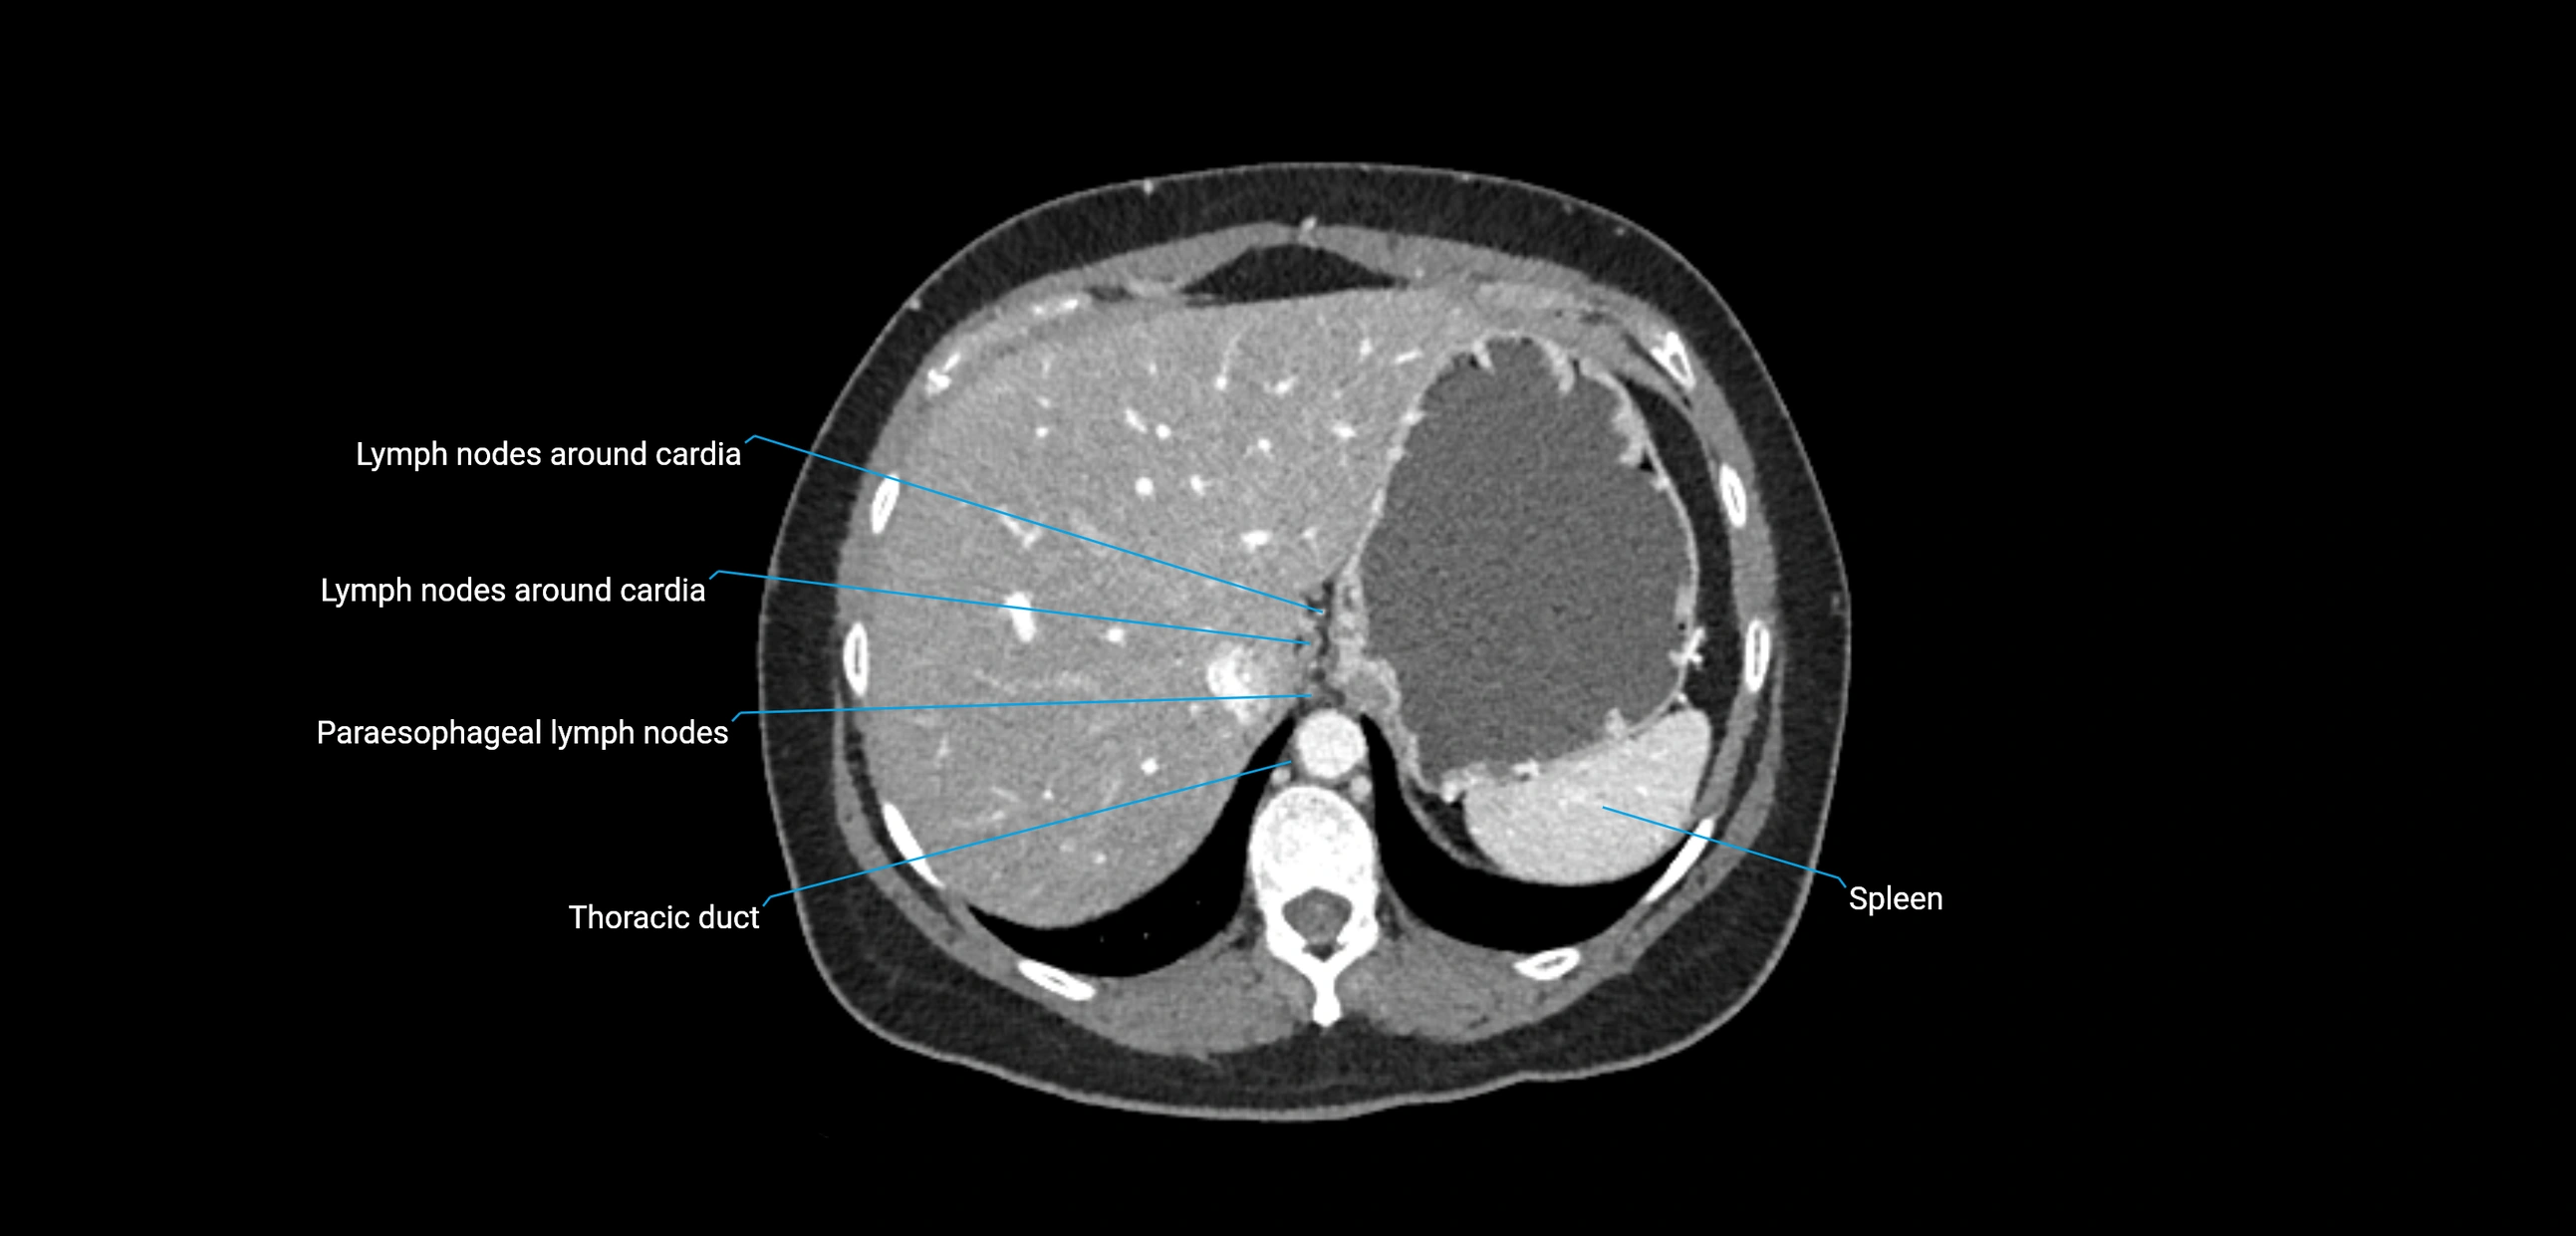

CT image

image